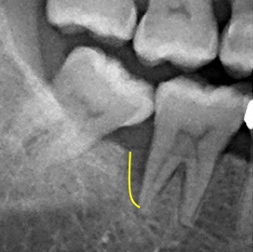

处理:刮除深层牙结石,将牙齿表面及深藏在牙齿下的牙结石用器械刮除乾净之后,配合药物深入牙周囊袋做深层灭菌

齿槽骨已长回80%,復塬状况良好齿槽骨内的骨头逐渐生长,骨头高度比治疗前高出甚多。